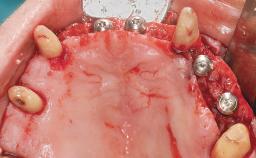

Conventional Loading of Eight Implants in the Maxilla and Final Restoration with a Full-Arch Gold-Ceramic FDP

A 35-year-old Caucasian female presenting with advanced periodontal disease involving both the maxillary and the mandibular dentition was referred for evaluation. The patient, a non-smoker in good general health, requested treatment for recurrent periodontal abscesses, tooth mobility, and discomfort during chewing, as well as restoration of her missing teeth with a fixed prosthesis to improve mastication and esthetics. All residual maxillary teeth exhibited plaque deposits, deep pockets, bleeding on probing, and class III mobility and were evaluated as hopeless. All residual mandibular teeth except tooth 37 could be maintained after periodontal therapy.

Bone Augmentation | Horizontal|Staged|Vertical |

Augmentation Materials | Autogenous block(s) |